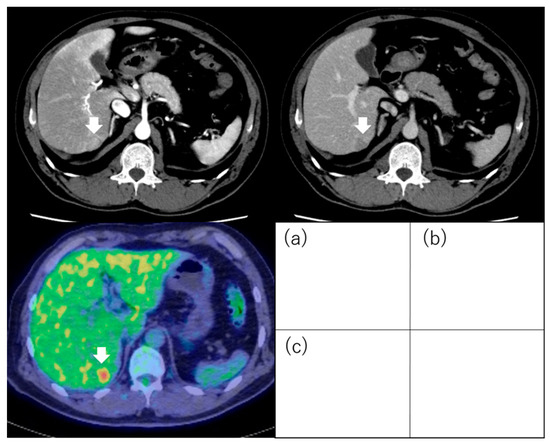

- Ida, Y.; Tamai, H.; Shingaki, N.; Shimizu, R.; Maeshima, S.; Maekita, T.; Iguchi, M.; Terada, M.; Kitano, M. Prognostic value of (18)F-fluorodeoxyglucose positron emission tomography in patients with small hepatocellular carcinoma treated by radiofrequency ablation. Cancer Imaging Off. Publ. Int. Cancer Imaging Soc. 2020, 20, 74. [Google Scholar] [CrossRef]

| Ida et al. [85] | 121 | ≤3 tumors and ≤3 cm | RFA | Outcome (recurrence, OS) | PET positivity was one of the independent factors for metastatic recurrence (HR, 10.297; 95% CI, 3.128–33.898; p < 0.001) and OS (HR, 7.300; 95% CI, 1.920–27.751; p = 0.004). |